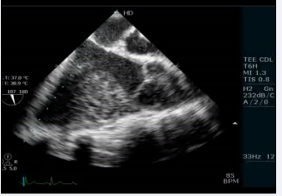

We performed transesophageal echocardiogram to define the anatomy and confirmed AV and VA concordance (video 4)

Video 4 :Transesophageal echocardiogram 4 chamber view showing AV and VA concordance with a doubtful VSD.

There were also sub pulmonary conus with pulmonary tricuspid discontinuity (video 6)

Video 6: Transesophageal echocardiogram long axis view showing subpulmonary conus with pulmonary tricuspid discontinuity

and a small ostium secundum atrial septal defect (left to right shunt). Furthermore, there was thickening of the interventricular septum that appeared as a pouch. The patient underwent cardiac catheterization to define the anatomy and determine the complexity because the VSD was not confirmed. The QP:Qs was 1:1. The left ventriculography revealed a normal contractile ventricle connected to the left sided aorta. There was no evidence of VSD. However, there was opacification of a small pouch just medial to the septum. There was no opacification of the pulmonary artery (Figure 5; video7)